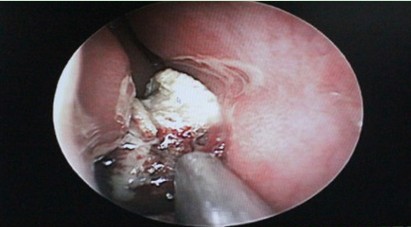

2013年1月5日,西安新城中大耳鼻喉医院为一例鼻结石患者施行了结石摘除术。